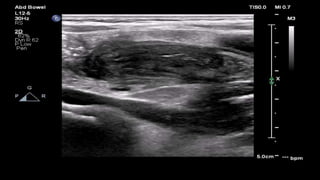

This document discusses the evaluation of right lower abdominal pain and lists appendicitis as a key cause. It notes that other potential causes include hemorrhagic cysts, heterotrophic pregnancy, salpingitis with pyosalpinx, funiculitis, and torsion of an undescended testis. The document was presented by Dr. A.S.M. Sufian of Cumilla Medical College Hospital and thanks the audience for their patience and listening.